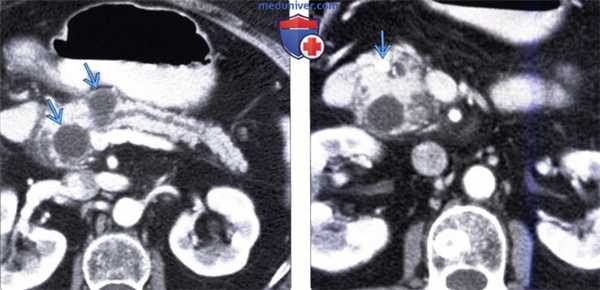

(Справа) На рентгенограмме (ЭРХПГ) визуализируется мелкий проток В в головке поджелудочной железы, начинающийся в проекции переднего правого края двенадцатиперстной кишки, огибающий ее, и открывающийся в главный панкреатический проток около ампулы. (Слева) На аксиальной КТ с контрастным усилением визуализируется поджелудочная железа, полностью окружающая двенадцатиперстную кишку. Обратите внимание на различное контрастное усиление поджелудочной железы и стенки двенадцатиперстной кишки.

(Справа) На сагиттальной КТ с контрастным усилением у этого же пациента определяется сужение двенадцатиперстной кишки, обусловленное наличием ткани поджелудочной железы спереди и сзади от нее. Несмотря на то, что в большинстве случаев у взрослых людей аннулярная поджелудочная железа никак себя не проявляет, у этого пациента периодически возникает обструкция двенадцатиперстной кишки, имеются жалобы на раннее насыщение.